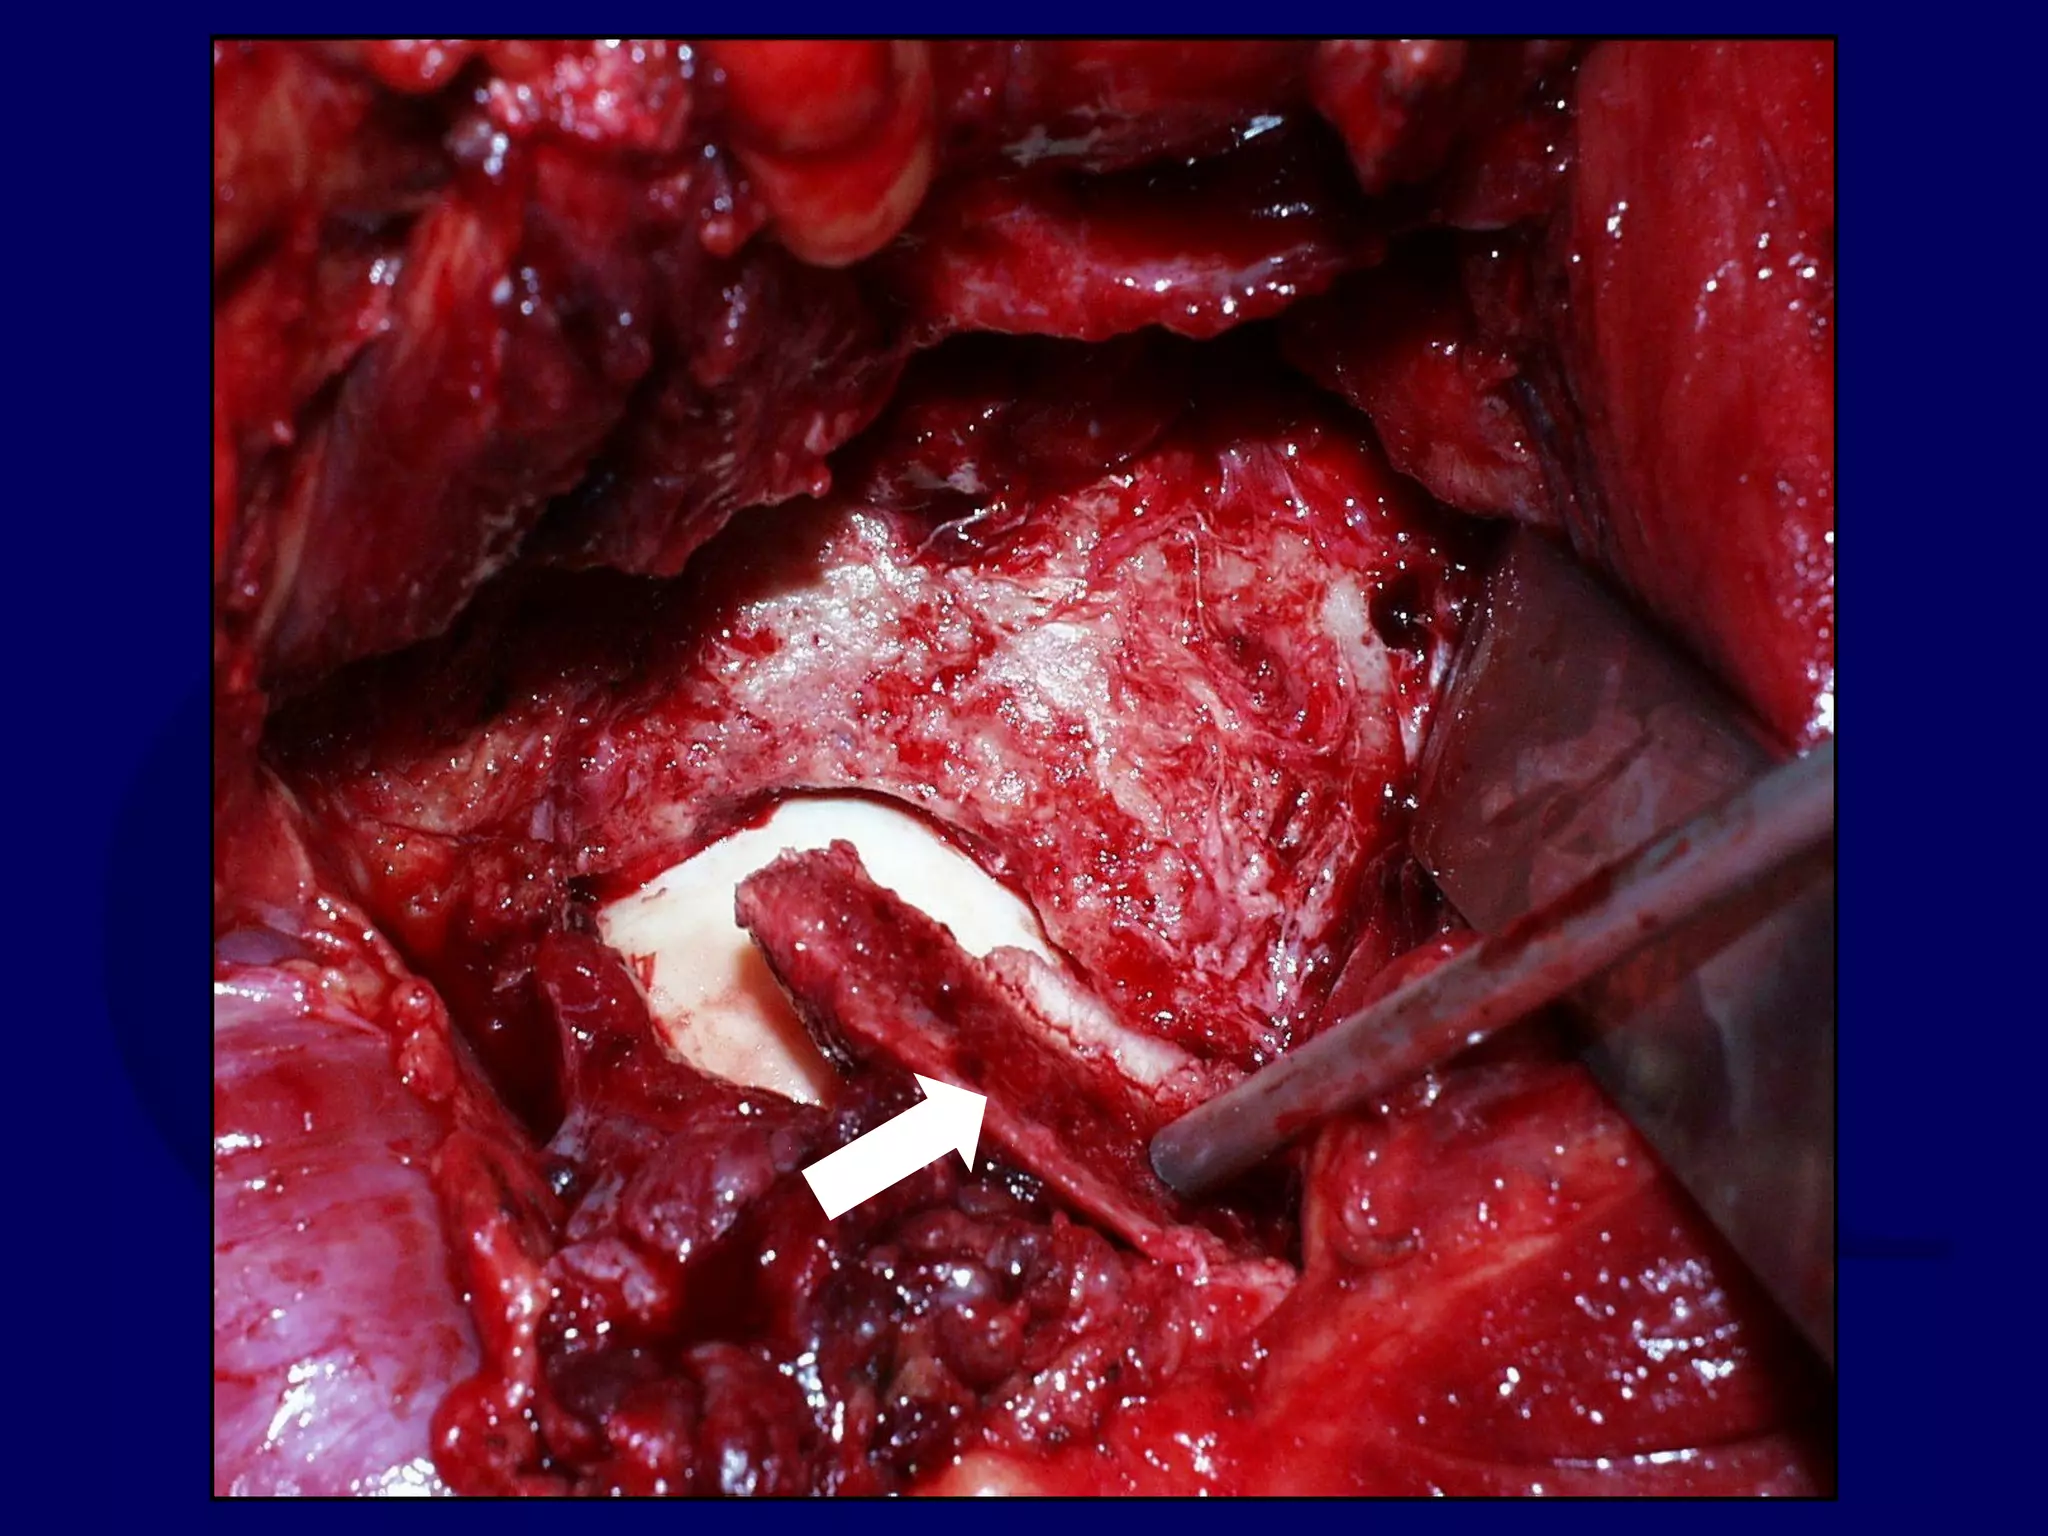

Posterior Wall Fractures

Posterior Wall Fxs:

Surgical Keys

• Avoid Devascularization of Fragment/s

• Remove Intra-articular Fragments

• Address Marginal Impaction

• Provide adequate buttress

• Avoid Over-Contouring of Plate